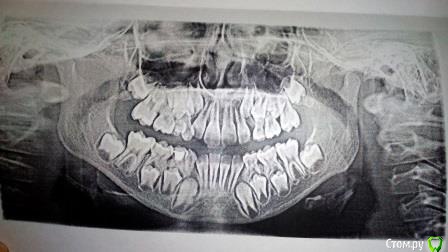

Здравствуйте, лечащий ортодонт считает, что нужно будет удалить коренные четверки. Сейчас носим пластинки уже полтора года. Подскажите, неужели без удаления не обойтись?

Может лучше прекратить ношение пластинок? Базис из акриловой  жесткой пластмассы, дуга, вон, вестибулярная, как ограничитель действует. Может там, конечно, винт есть, но аппарат явно из рода  механического действия. Сбросьте эти "оковы", дайте хоть малейший шанс для развития жевательного аппарата. К ЛОР врачу сводите ребенка, если еще не ходили: про аденоиды поспрашивайте, нагрузку жевательную увеличьте за счет рационального питания (мясо цельное отварное, хлебушек деревенский-крестьянского типа). У Вашей девочки типичное урбанистическое формирование зубо-челюстной системы. А об удалении вторых премоляров заикаться еще рано. Совсем рано.

С какой целью вообще решили носить пластинку? не ровный боковой резец??? ну и что! они еще все немного неровные будут , тогда и пластинку сделаете и с винтом обязательно!!!  Вашим аппаратом просто пытаются впихнуть зуб в зубной ряд, а ему там мало место. отсюда вывод- не надо его впихивать, надо просто создать место!  расширять винтом. Но я в таких случаях вообще ничего не делаю- просто надо увеличить естественную жевательную нагрузку, наблюдаться. и может чуть позже - аппаратурное лечение. Про удаление четверок - вопрос абсолютно не стоит!